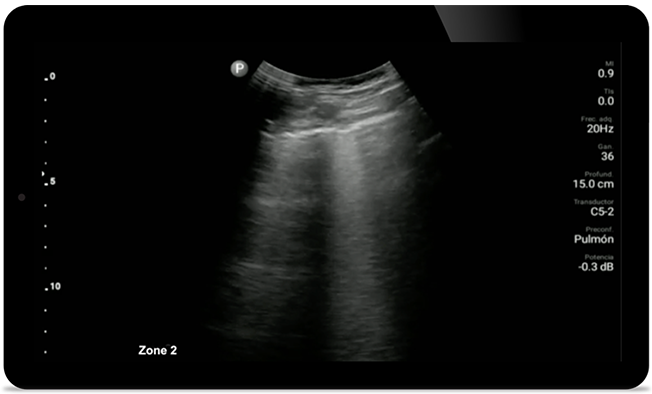

Esté atento a la neumonía por COVID

Lumify puede ayudar a obtener resultados similares a los de una tomografía computarizada de tórax al evaluar la neumonía y el síndrome de dificultad respiratoria en adultos.